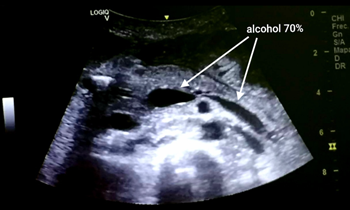

Upon reaching the plexus, 10ml of 0.5% bupivacaine was first injected in order to determine the effectiveness of the block and provide local analgesia. Subsequently, 20ml of 70% alcohol was injected around the celiac plexus. The patient manifested a decrease in pain five minutes after the injection. At 6hours after neurolysis, the patient had only upon reaching the plexus, 10ml of 0.5% bupivacaine was first injected in order to determine the effectiveness of the block and provide local analgesia. Subsequently, 20ml of 70% alcohol was injected into the antecrural space (Figure 1).

Figure 1 Diffusion of the neurolytic agent in the space anterior to the celiac plexus.

The patient manifested a decrease in pain five minutes after the injection. At 6 hours after neurolysis, the patient had only mild abdominal discomfort (VAS=2). She did not present any dynamic instability after the procedure performed, but she had mild diarrhea the day after the procedure that quickly subsided. The patient was discharged 48 hours after the procedure without pain (VAS=0). One week after CPN the decrease in pain severity was maintained at the same level.